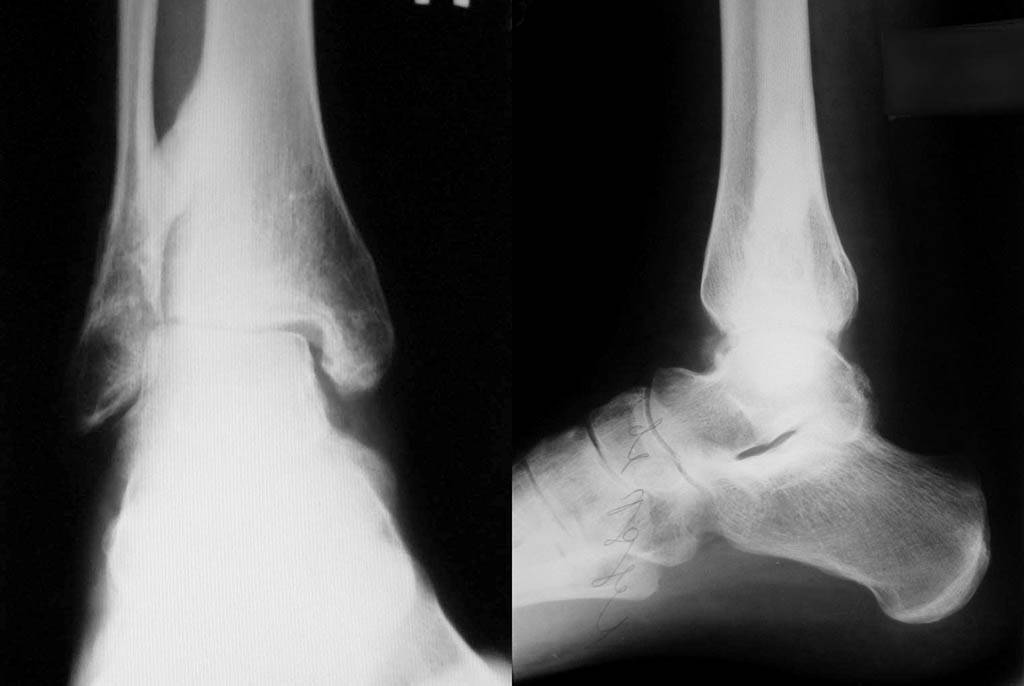

Приложил последние снимки г/стопа.

Стадия артроза определяется еще и клиникой. Но и рентгенологическая картина тут более чем достаточная. И нарушенные взаимоотношения в

суставе налицо, и вторичные изменения. Группа и сейчас вполне уместна.